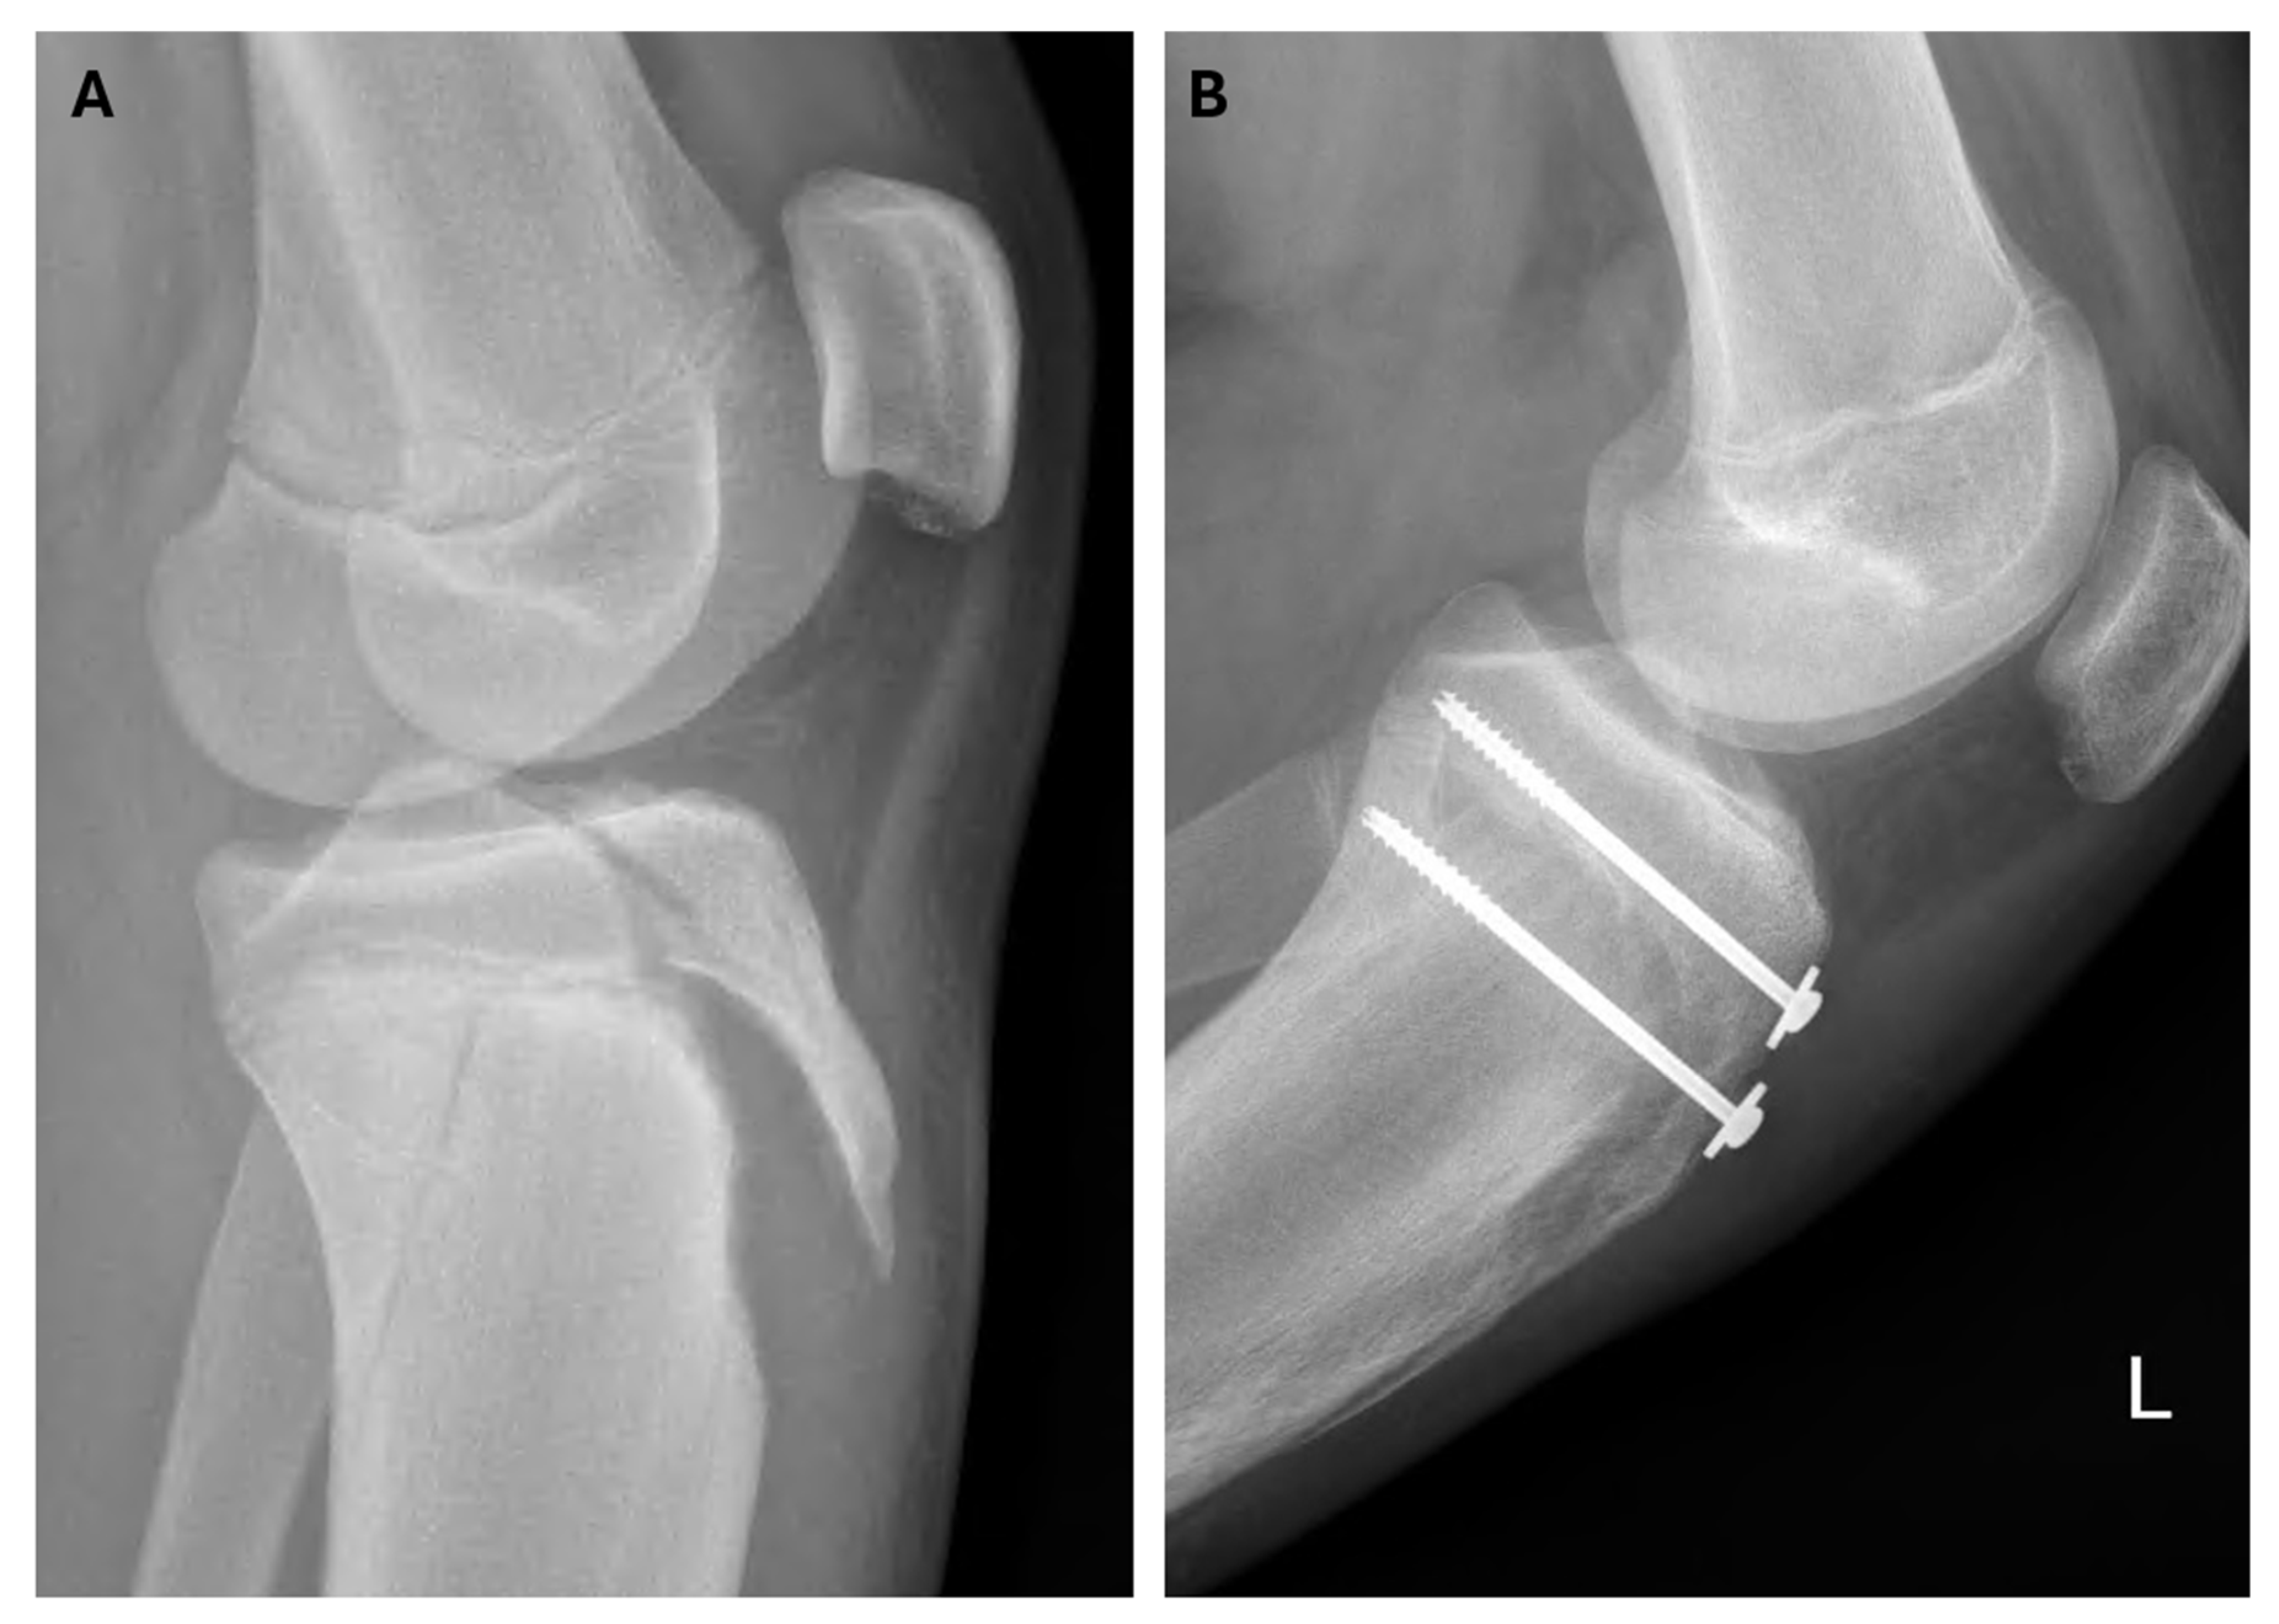

| 9 | Soccer | CT | IVb | ORIF | screws | patellar ligament | - | 7.8 |

| 16 | Soccer | - | IVb | ORIF | screws | - | - | 10.2 |

| 17 | Running | CT | IVb | ORIF | screws | patellar ligament | - | 7.2 |